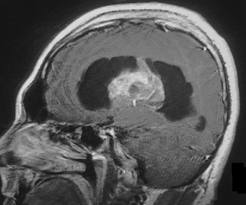

P.S.: Para los interesados… Tumor intraventricular con hidrocefalia.